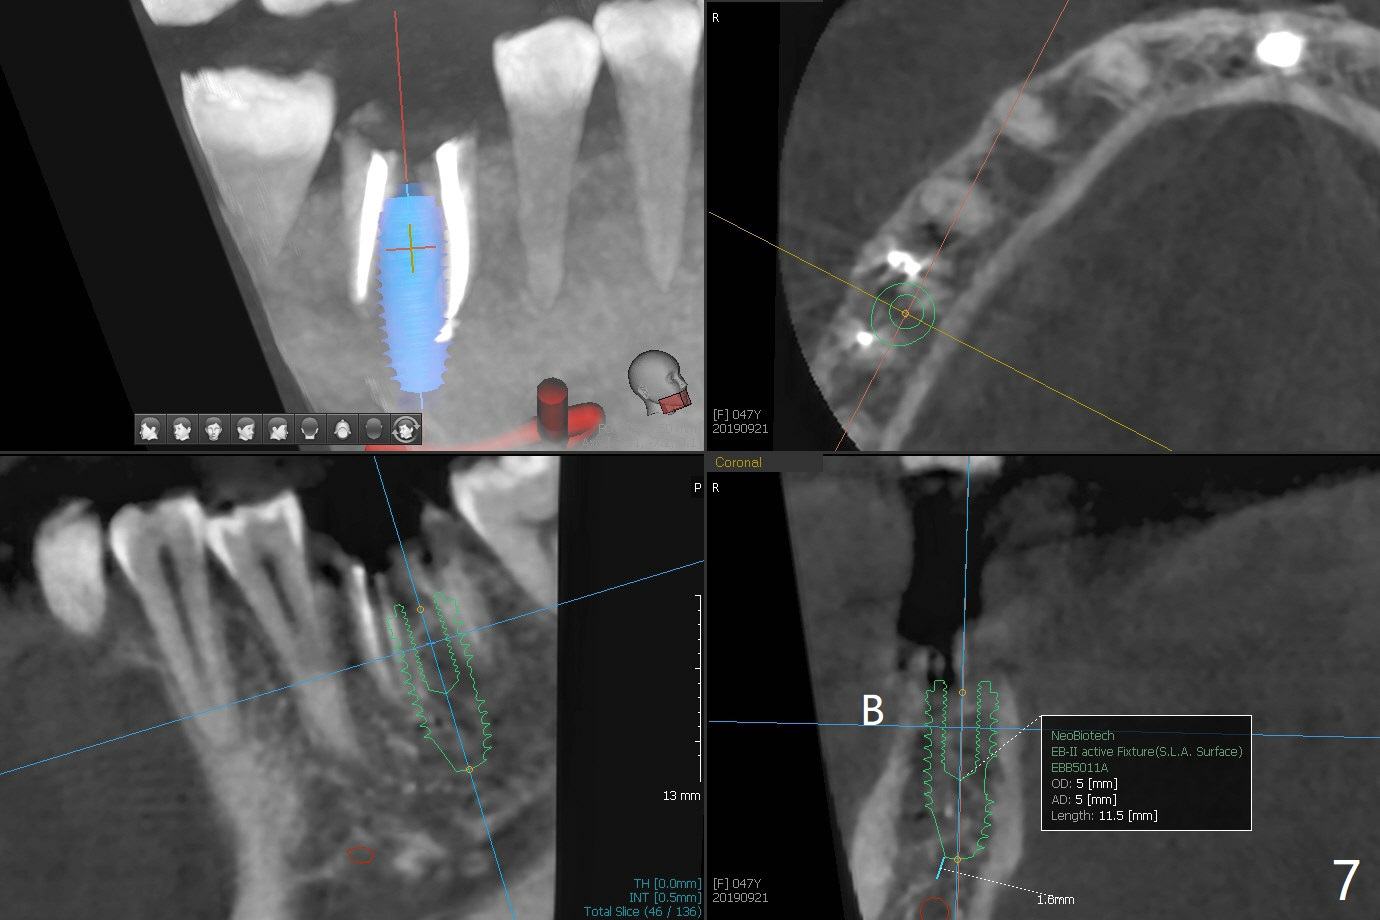

A 47-year-old woman with one carious tooth in her mouth (at #30) received RCT 14 years ago (Fig.1). The molar survives without crown for 3.5 years (Fig.2) and with crown for 8 years (Fig.3). The tooth has 2nd decays 10 years post crown (14 years post RCT, Fig.4 *). The crown dislodges 2 months later (Fig.5). Does the crown inadvertently reduce the longevity of the tooth simply hampering oral hygiene? After osteotomy until 4.5x10 or 13 mm IS drill with guide and 5 mm Bicon reamer free hand, place either 5x6 or 11 mm Bicon implant (Fig.6). Keep the black insertion plug to hold periodontal dressing or a provisional, which will be bonded to the neighboring tooth. Prepare PRFx1 for sticky bone around the not-so-stable implant. A 5x11.5 mm bone-level implant is planned by CT (Fig.7). Socket shield will be conducted to reduce buccal plate collapse. If the osteotomy depth is 10 mm due to limited mouth opening, place 4.5x6 mm Bicon implant. Otherwise 4.5x8 mm one. Return to Lower Molar Immediate Implant, Prevent Molar Periimplantitis (Protocols, Table), Trajectory II, Metronidazole Early Intervention Xin Wei, DDS, PhD, MS 1st edition 09/01/2019, last revision 11/10/2019